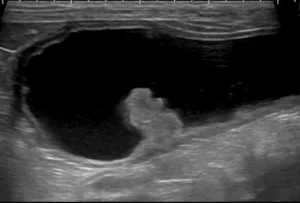

腹部超音波検査

前立腺腫瘍の拡がり、膀胱、腎臓、腰下リンパ節群を中心に評価します。

前立腺の石灰化を認める場合には、前立腺癌を疑います。